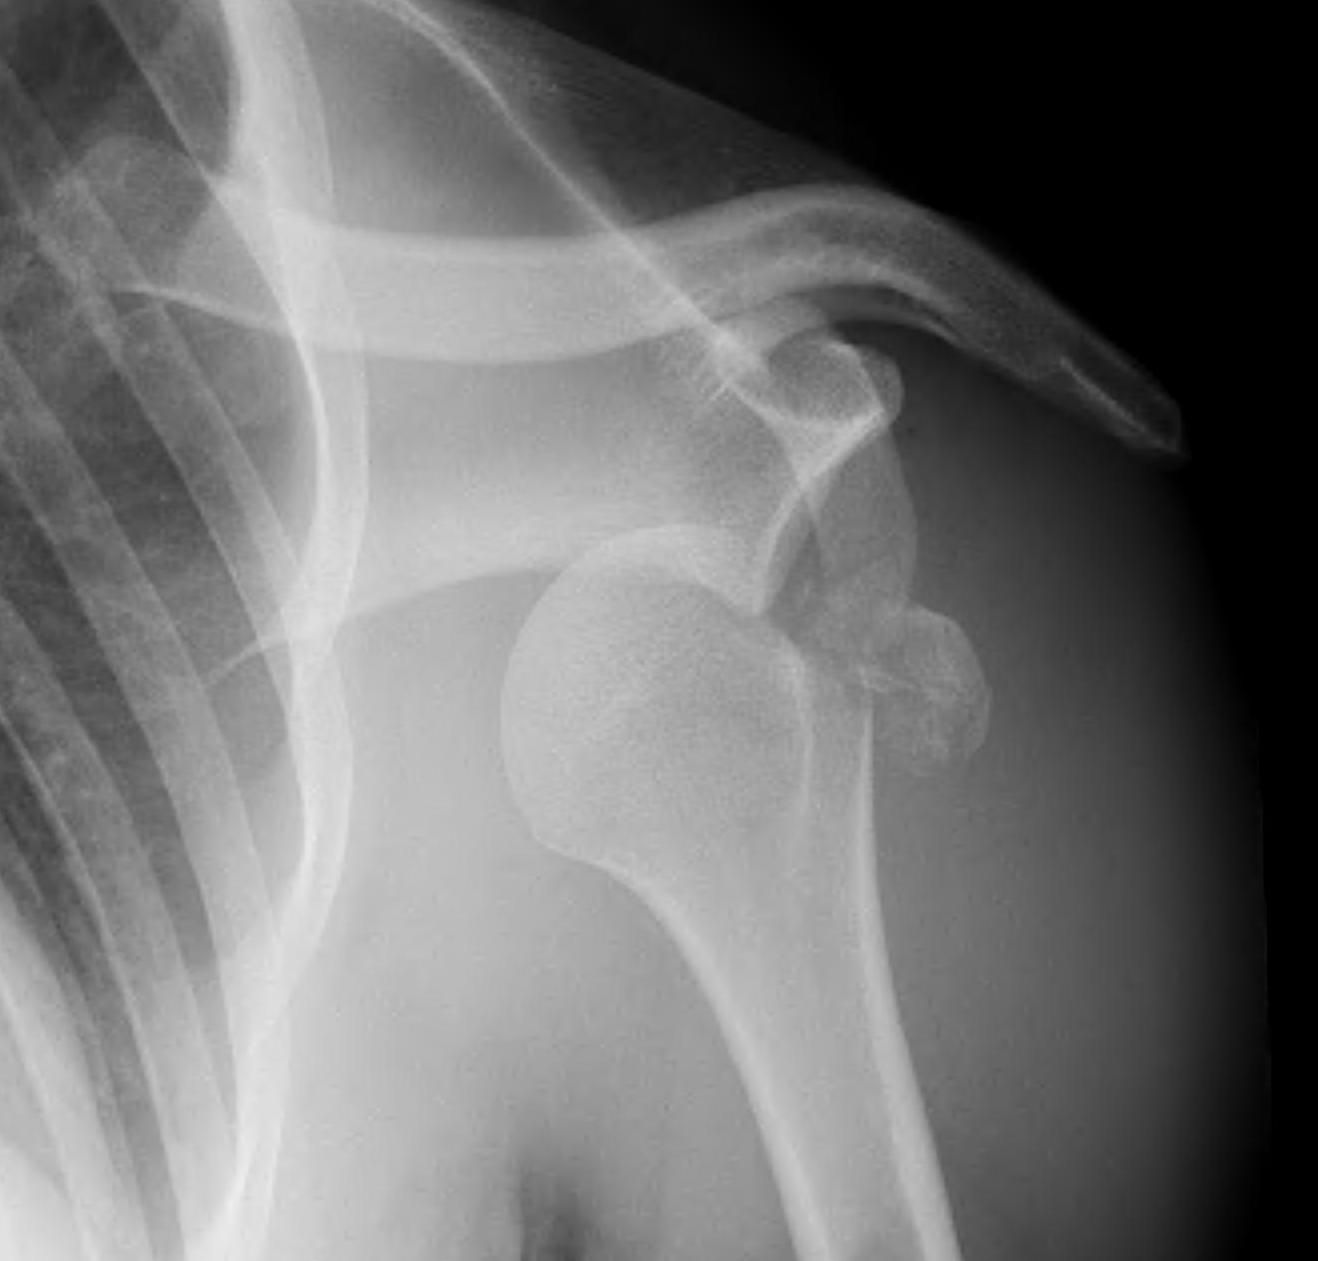

Xray

True AP

Scapular Lateral

Axillary Lateral

Garth (aim beam caudally)

Greater tuberosity fractures

Indications

- > 5 mm displacement

Management

- ORIF with plate

- screw + suture repair

- screw alone in young patient